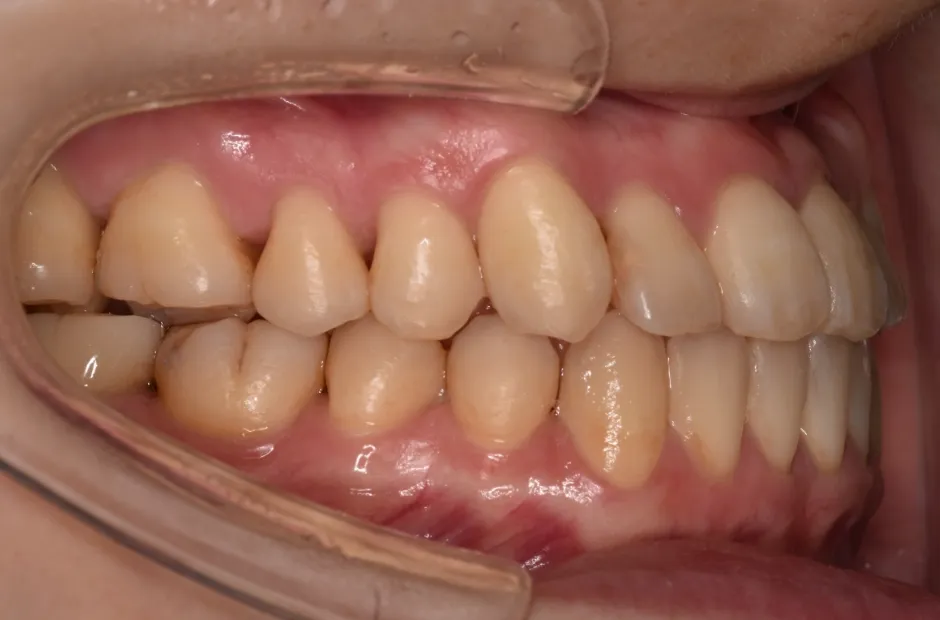

叢生

| 診断名・主訴 | 叢生 |

|---|---|

| 年齢・性別 | 43歳・女性 |

| 治療期間・回数 | 2年7か月 27回 |

| 治療に用いた主な装置 | 舌側矯正 |

| 抜歯部位 | 両顎4,4 |

| 治療費 | 100万円(税抜) |

| リスク・副作用 | 装置による違和感・疼痛・歯肉退縮・歯根吸収・虫歯のリスクなど |

治療後